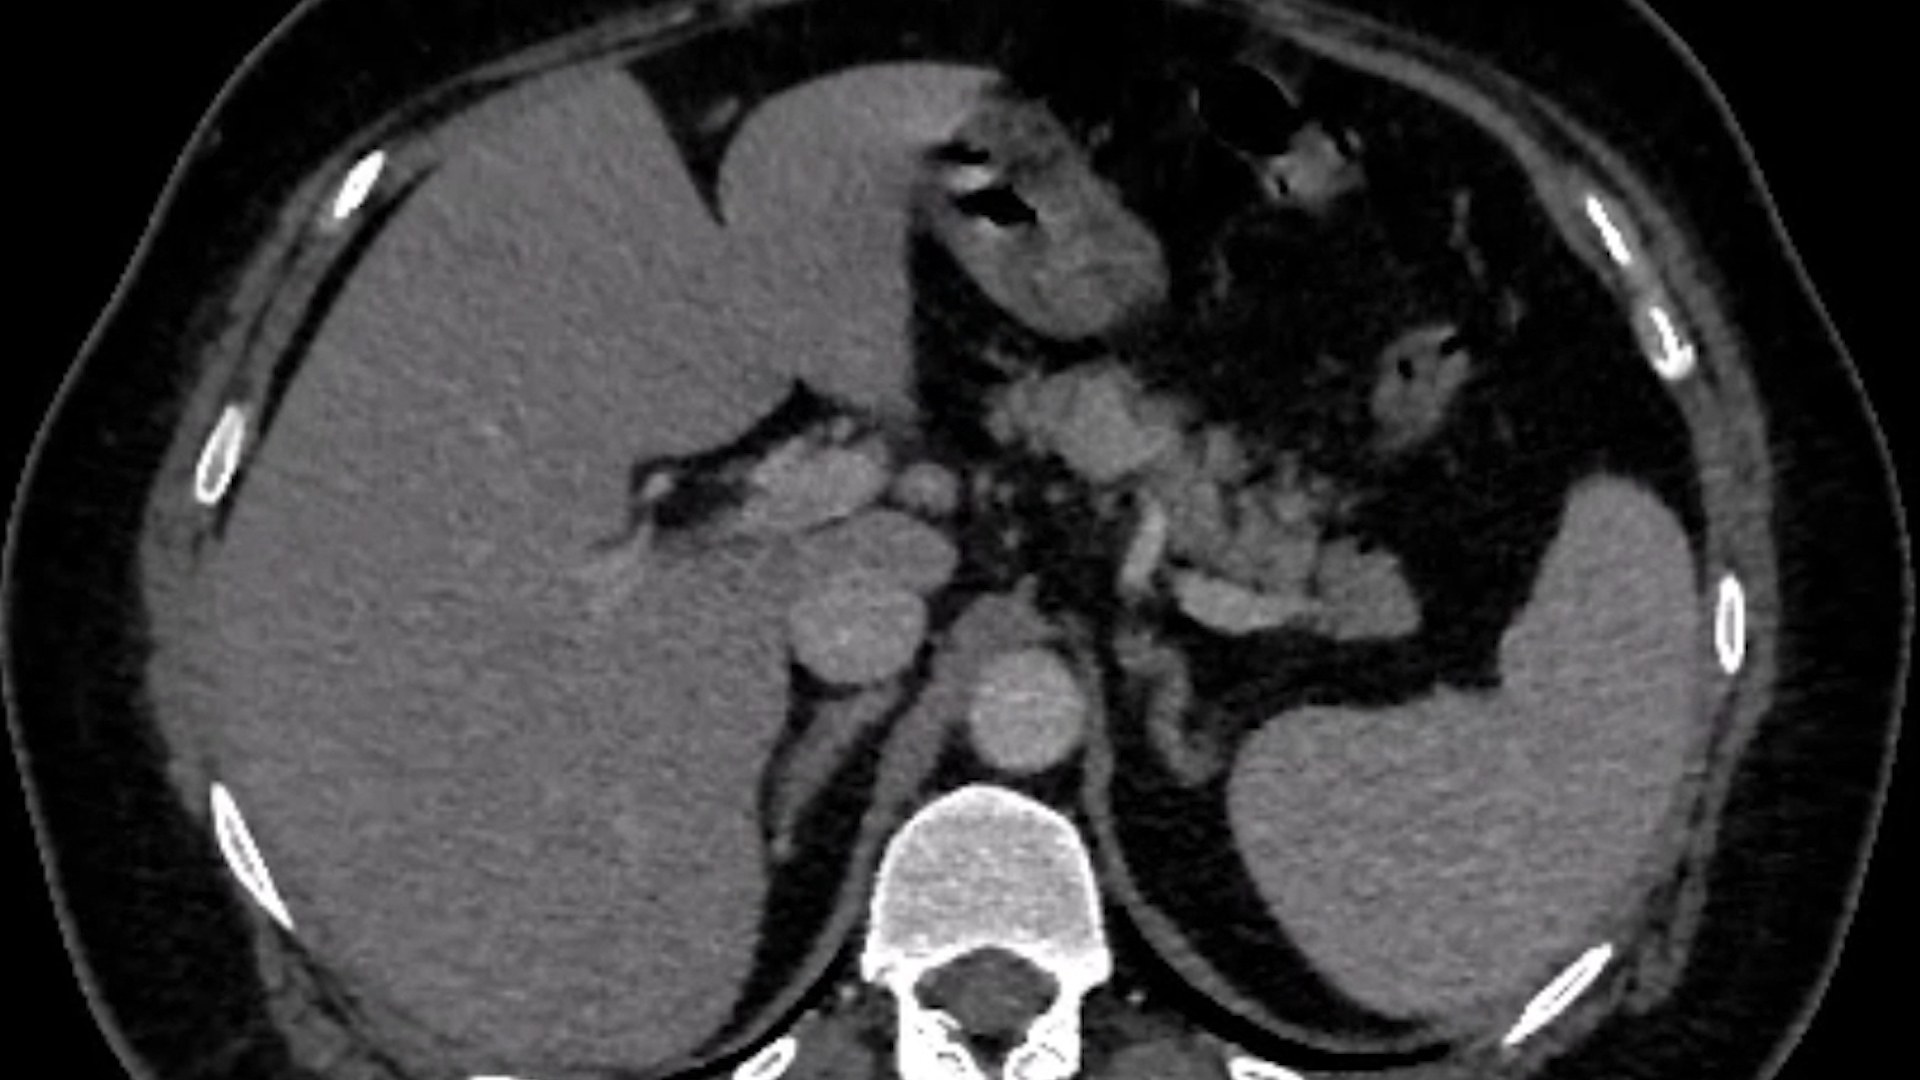

We present the case of a 43-year-old woman with emergency surgery for a hemorrhagic ovarian cyst, with intraoperative biopsy of a pancreatic cystic formation, followed by 2 episodes of acute pancreatitis, with the formation in 3 months of a pseudocyst of approx. 7 cm, in the vicinity of the pancreatic corporeal cyst formation (IPMN – intrapapillary mucinous neoplasm) (Figure 1).

Abdominal CT scan + MRI: 2 adjacent cystic formations (suggestive of IPMN and pseudocyst, both communicating with the duct of Wirsung which was dilated towards the tail of the pancreas!).